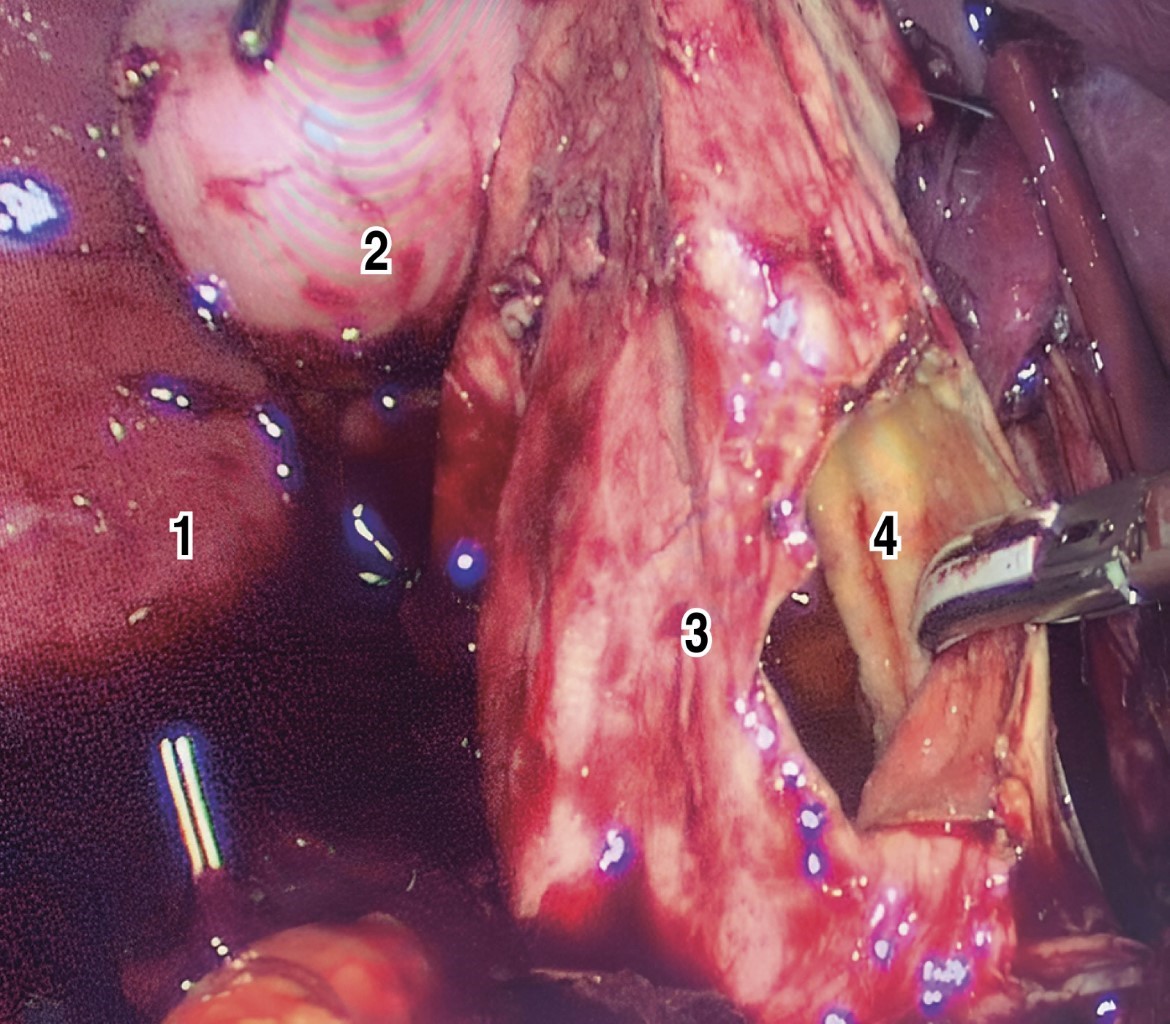

Elective resection was scheduled laparoscopically (Figure 5) after completing a thorough preoperative protocol. Intraoperative findings evidenced a QC-IVA-Todani-modified, with an atrophic gallbladder. Dissection of the cyst capsule was initiated by attempting to separate it from the vascular structures (portal vein and hepatic artery). It was decided to open the cyst to facilitate its dissection. However, due to its strong adhesion and vascularization, with scarce but continuous bleeding, it was converted to open surgery through a Kocher-type incision.

Dissection of the cyst was continued by separating it from the portal vein without damaging it. A Bakes dilator was introduced through the cyst opening to identify and canalize the dilated right and left hepatic ducts. Then, the removal of the common bile duct cyst was performed from the bifurcation of both intrahepatic ducts to the duodenal border, where a continuous suture with polydioxanone was performed, including the last centimeter of the common bile duct, thus performing a complete removal of the cyst, including the gallbladder. Finally, a Roux-en-Y biliodigestive bypass was performed, with a jejunal loop of 50 cm from the Treitz angle and a biliary drainage loop of 50 cm, using a 60 mm linear stapler in the hepatic-jejunal anastomosis.

However, due to the firm adhesion of the posterior wall of the cyst to the vascular structures, mainly to the portal vein, laparoscopic resection was not possible, and it became an open surgery through a Kocher-type incision. In this way, its total extirpation was achieved, leaving a remnant of the duct in the intrapancreatic portion of about 5 mm. The literature indicates that this remnant can be the cause of dysplasia.11,12 However, we do not fully agree with this statement because the physiopathology of the cyst is modified when most of the cystic lesion is removed, thus eliminating the increase of pressure in the biliary tract.